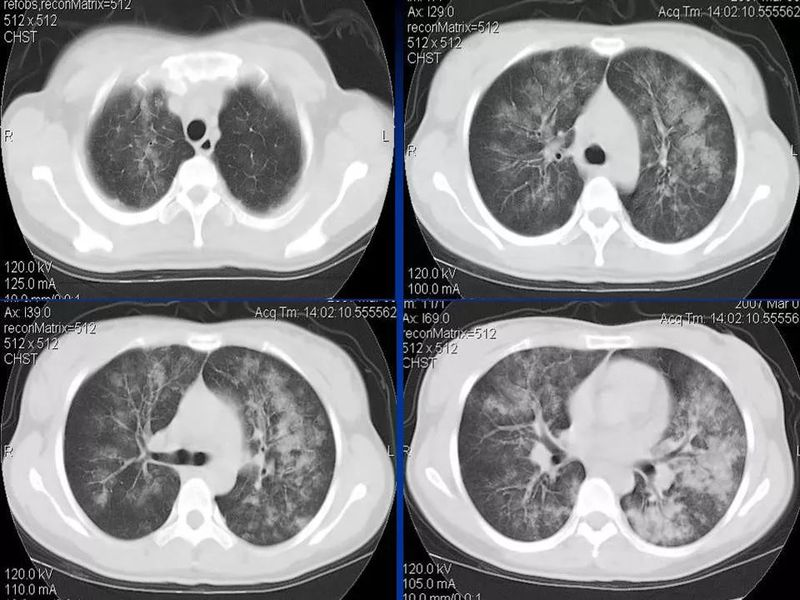

主任提醒:这个病很容易误诊为肺炎!